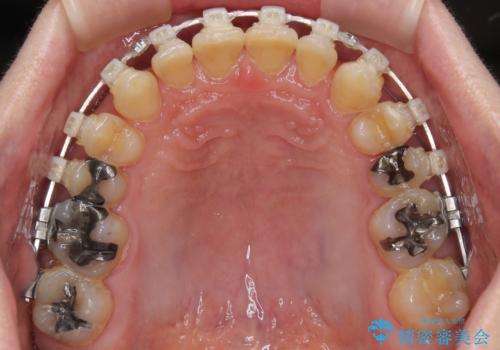

- 矯正装置

- クリアブラケット

手前に傾斜している奥歯をワイヤー装置で立ち上がらせ、咬み合わせの高さを挙上することで突き上げを解消し、空隙歯列を改善していくこととしました。